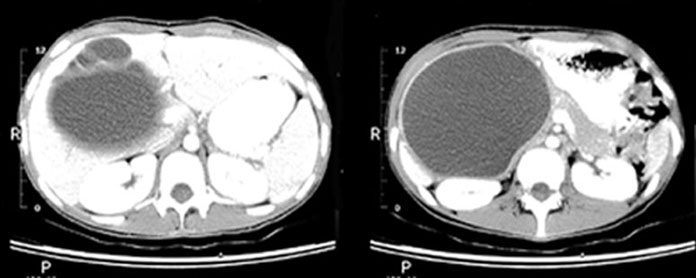

Large cystic lesion in location of common bile duct

Nuclear medicine hepatobiliary scan demonstrates cystic dilatation of the common bile duct and dilatation of the intrahepatic bile ducts secondary to obstruction